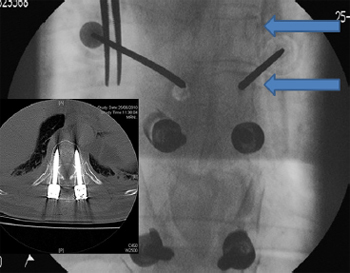

Fig. 6. Anterior/posterior image intensifier (II) radiographs showing percutaneous

cannulation of small pedicles. Angulating the II machine so that the surgeon is

looking down the pedicle – the ''bulls eye'' view (arrows) – assists in placement in

difficult pedicles. (Insert) The II technique results in highly accurate pedicle screw

insertion – a 5.5 mm screw into a 6 mm pedicle.

4.3. Cannulation of small pedicles

The senior author has placed percutaneous pedicle screws as

high as T4 in patients with tumour and trauma; however, percutaneous

pedicle placement high in the thoracic spine can be technically

difficult due to the small pedicle sizes in the mid-upper thoracic

spine and the change in pedicle angulation at the T1 to T4 levels.

The greatest challenge, however, for percutaneous placement in

the thoracic spine is from small pedicles. Cannulation of small pedicles

involves careful evaluation of the pre-operative CT scans and

and AP radiographs to ensure that the pedicle can be cannulated.

The pedicle must have a width of at least 3 mm to 4 mm so that

the Jamshidi needle can be navigated down the pedicle. The surgeon

must have an excellent view of the pedicle prior to attempting cannulation

of a small diameter pedicle. This involves small movements

of the gantry of the II machine so that the II is directed in a ''bull's

eye'' view down the pedicle (Fig. 6). Due to the greater degree of

accuracy of the II technique (Fig. 6) over stereotaxis, the senior

author recommends II for small pedicle cannulation.